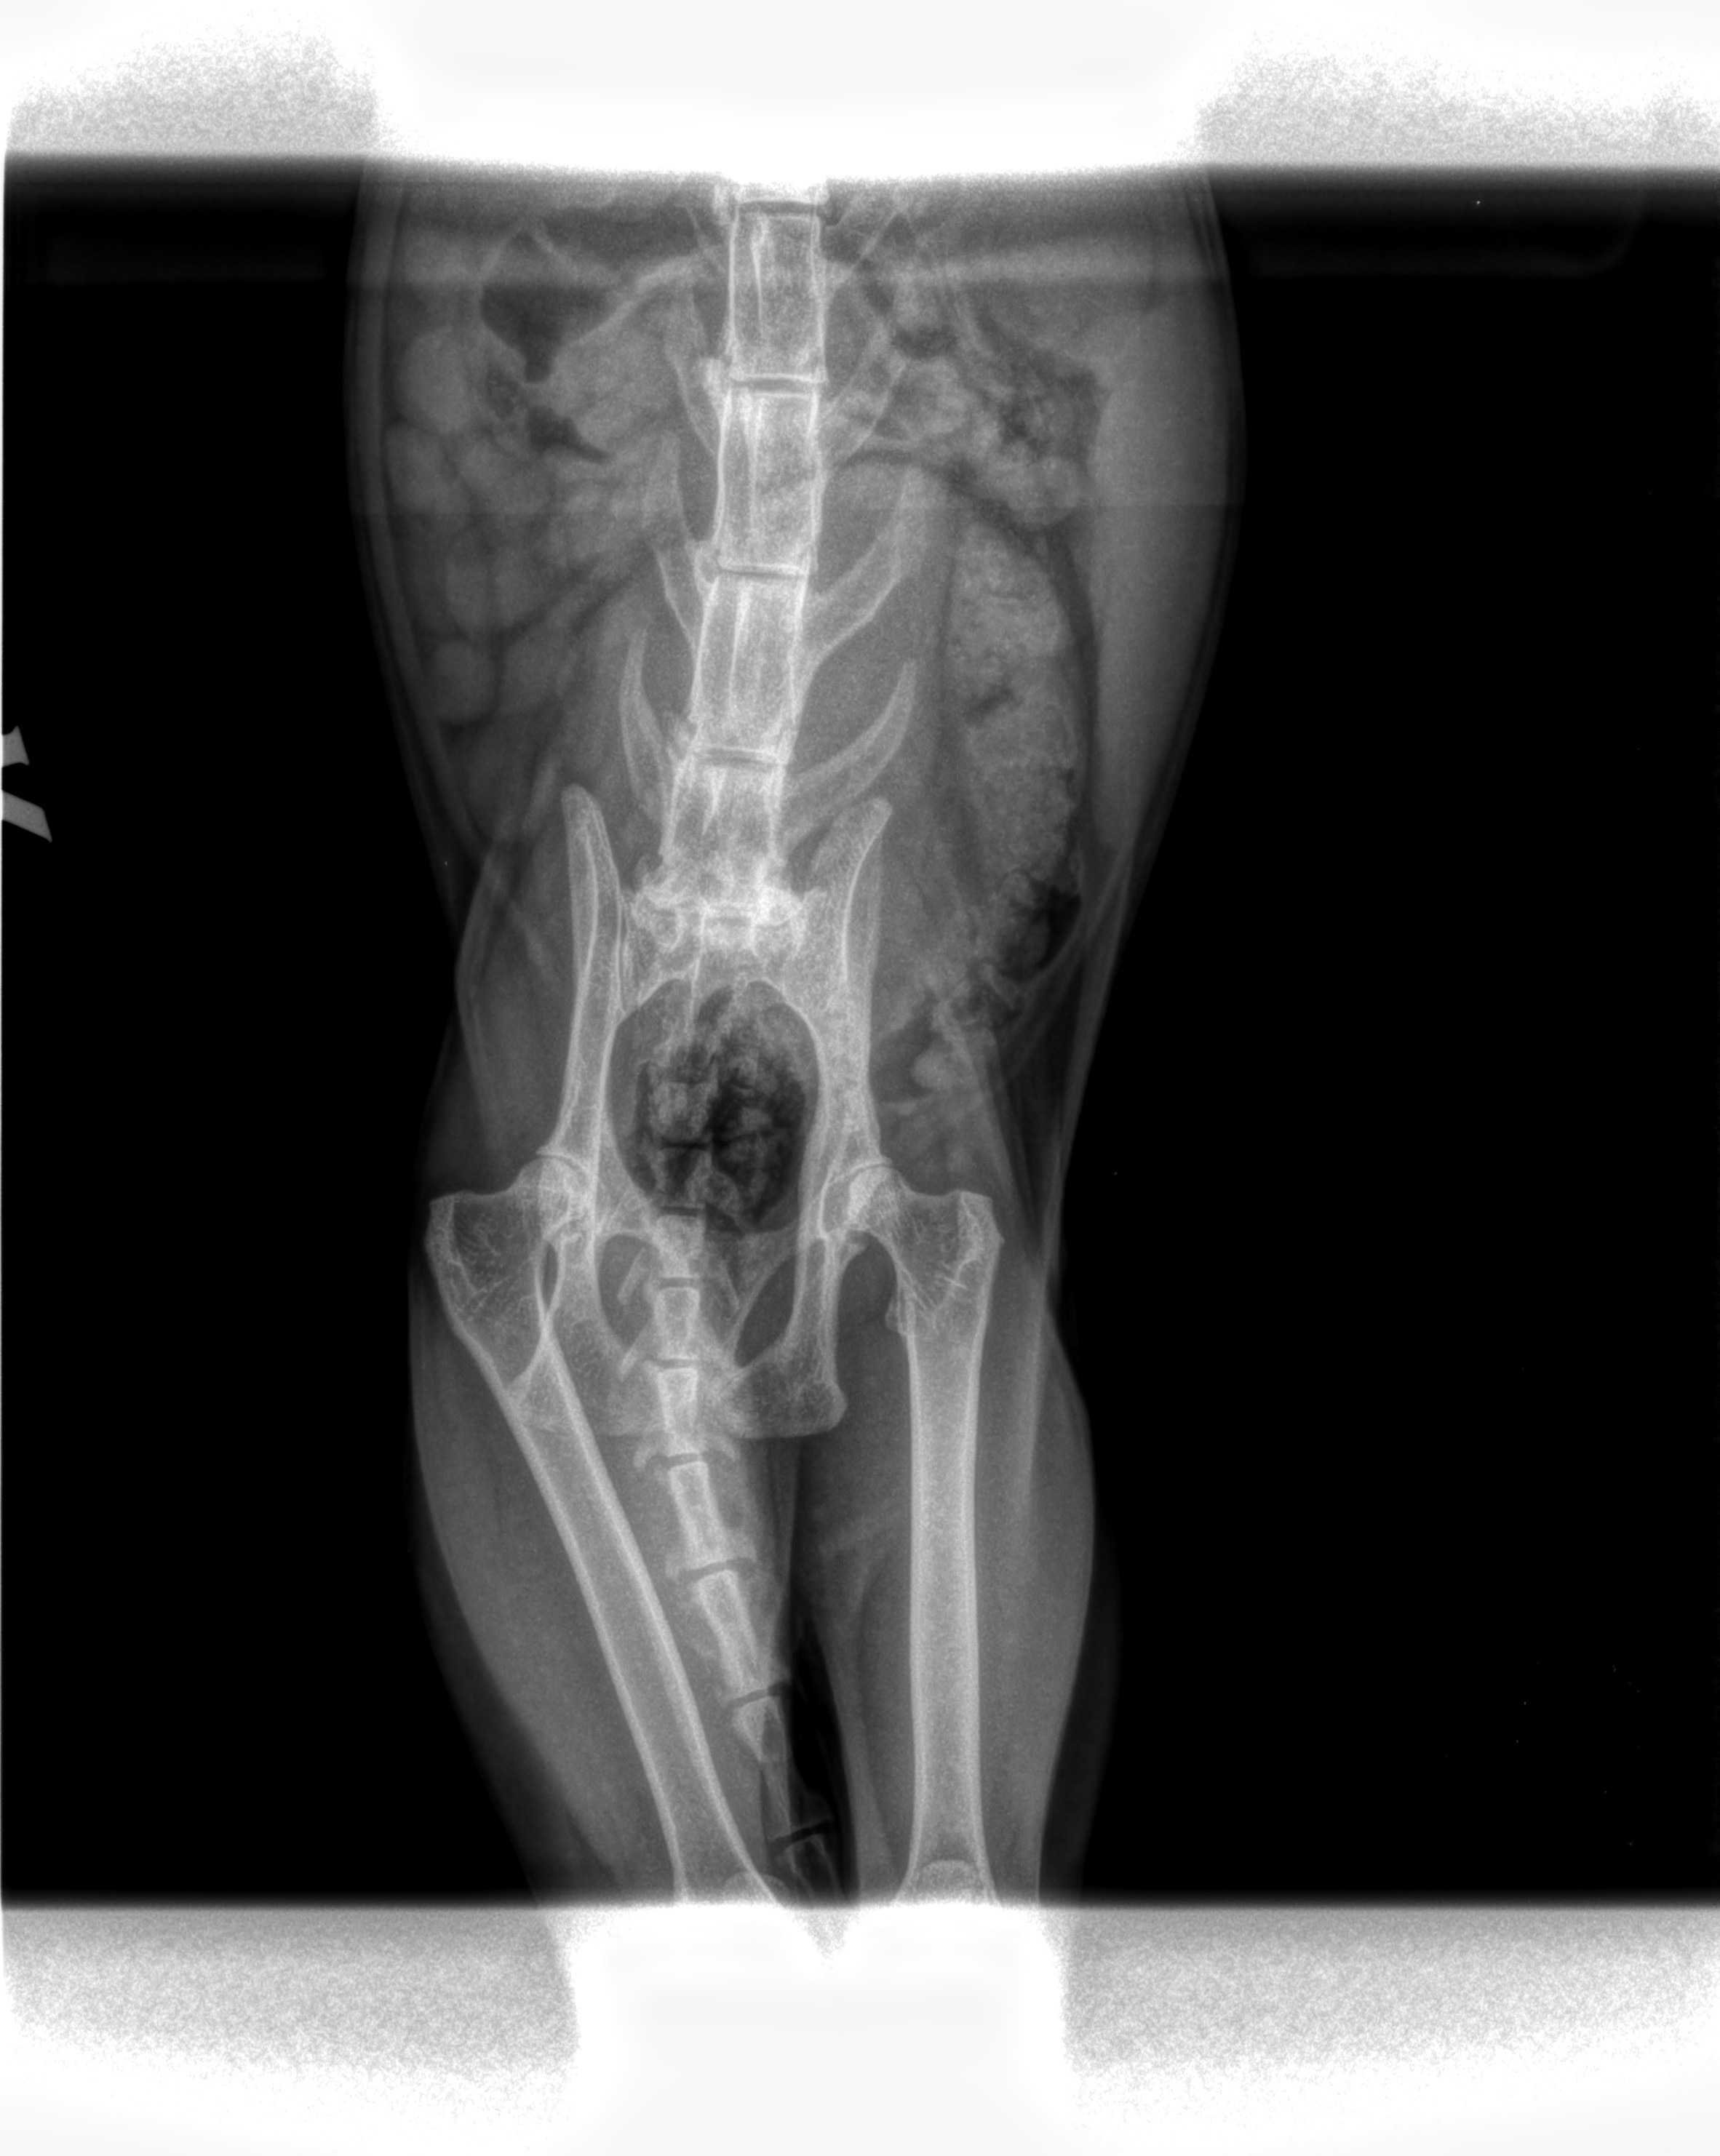

Recently, Twiggy suddenly started hobbling around on just three legs and went off his food. My mum rushed him to the vet, and after initial X-rays, our home vet suspected a severe hip fracture that would require complex surgery.

Crucial Update: Today (30/10/2025), Twiggy was seen by a specialist referral orthopaedic vet. This vet performed new scans and sedation, and they disagree with the initial diagnosis. This means we don't yet have an answer for why Twiggy is in such severe pain.